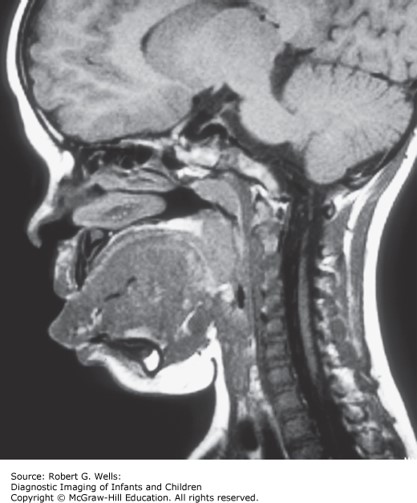

She is noted to have facial hemangiomata, pits on the backs of her ear helices, and double creases in her earlobes. Abdominal ultrasound reveals enlarged, lobulated kidneys.

The correct answer is A. The child has Beckwith–Wiedemann syndrome. These patients generally do quite well cognitively unless there are problems with untreated hypoglycemia in infancy. The other features on the list are possible complications of Beckwith–Wiedemann, but have not been associated with the development of cognitive impairment. (Chapter 176: "Syndromes of Multiple Congenital Anomalies/Dysplasias: Introduction" and Chapter 177: "Craniofacial Disorders: Introduction")

Photo: Wells RG. Diagnostic Imaging of Infants and Children; 2015.